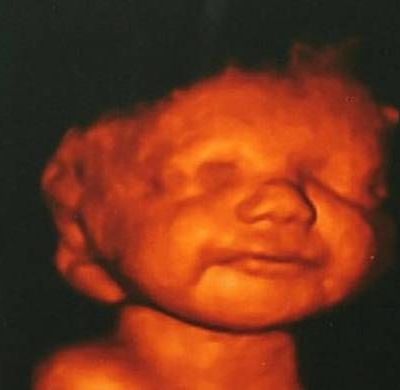

Είδε το αγέννητο μωρό της να χαμογελά και δεν έκανε έκτρωση